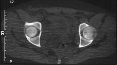

Radiographs:

Radiographs revealed a vertical buckle fracture of the right inferior sacrum, oblique fractures of the superior and inferior rami on the right and a fracture through the medial acetabulum. Obturator and iliac oblique inlet and outlet pelvic views, and a thin cut CT with 3-D reconstruction of the acetabulum were performed. These elucidated a comminuted anterior wall with fracture line extending to the posterior column. The posterior column was non-displaced. The pelvic fracture was non-displaced.

COMPUTED TOMOGRAPHY: R/O intra-articular loose fragments, Plan for surgery.